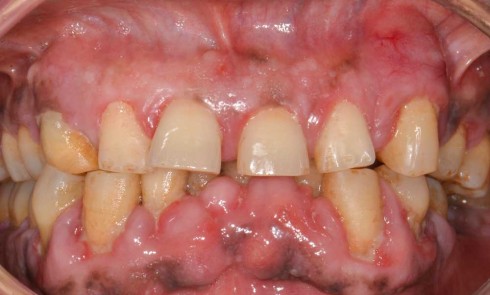

Quelles sont les 7 formes cliniques des épulis ? 1. Épulis inflammatoire (plasmocytaire) Nodule indolore, pédiculé, érythémateux, parfois ulcéré (fig. 1a)....